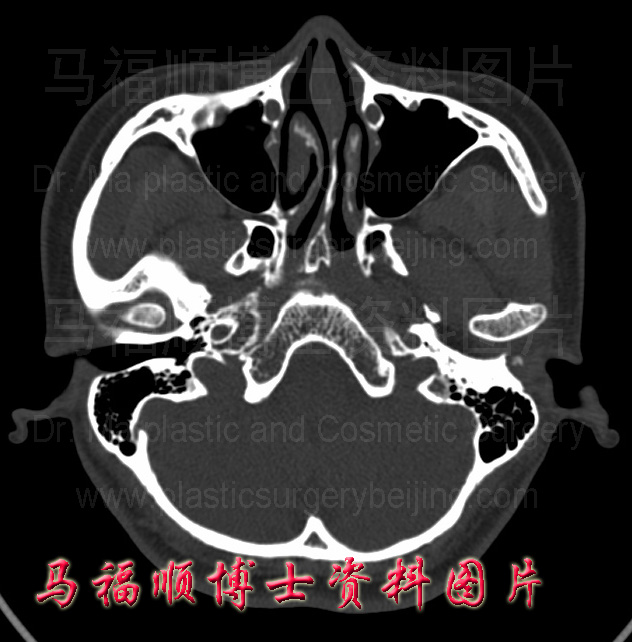

颧弓宽者的颧弓断层CT中显示颧弓的弓度大,向外侧突出明显。右侧颧弓窄者的CT断层片示颧弓的弓度小,平直。